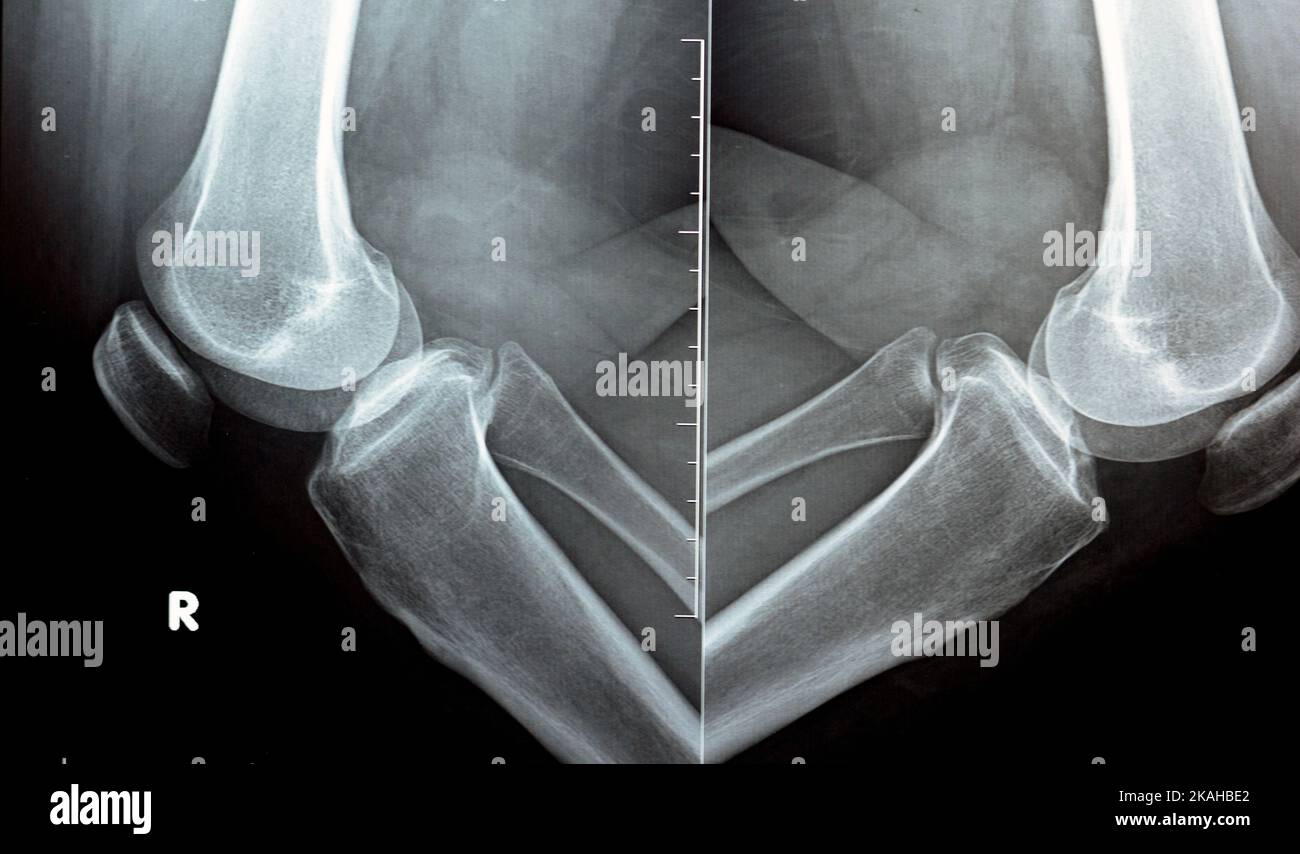

Severe Knee OA and radiological changes. In this left knee radiography

Severe Knee OA and radiological changes. In this left knee radiography What Is Articular Sclerosis Subchondral bone sclerosis, together with progressive cartilage degradation, is widely considered as a hallmark of oa. It shows up in the later stages of osteoarthritis. If you’ve been diagnosed with. Subchondral sclerosis is the hardening of the tip of a bone just below the cartilage. Despite the increase in bone volume. Osteoarthritis can cause bone thickening. Subchondral sclerosis is a. What Is Articular Sclerosis.